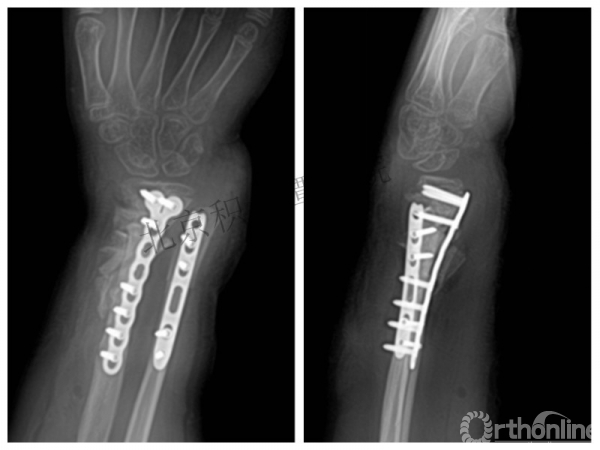

病例分享六

7岁、男孩,桡骨远端骨折

原始损伤片

手法整复后 - 45分钟!

伤后4天复查

伤后30天!

医生的处理方法!——医生终于没有坚持自己的原则!

伤后40天—切开复位内固定!

伤后18个月